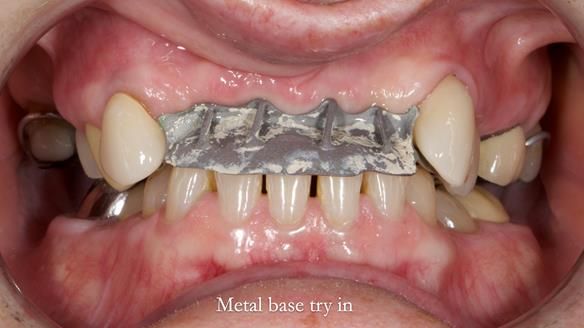

- Metalwork framework try-in – to verify fit, path of insertion, and support.